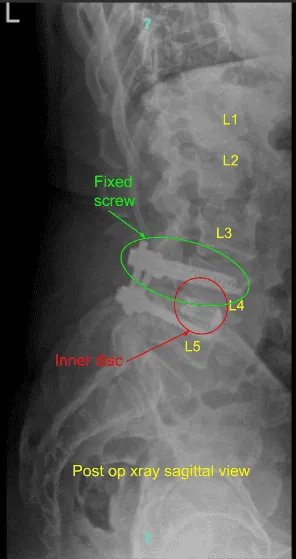

Se abrió una pequeña BMP en preparación para la fusión. La descompresión de revisión de L4-5 se realizó con laminectomía inferior de L3. El hueso se utilizaba para autoinjertos locales. Se realizó una descompresión completa de las L4 y L5 de la izquierda y derecha con curettes seguidas de punzón Kerrison. Se podía lograr una descompresión completa. Se colocó un nuevo tornillo de ajuste en la L4 izquierda y se apretó de la manera habitual.

La siguiente visita al consultorio del paciente fue una semana después de la descompresión L3-5 y la PSF en L4-5 con mejora de la afectación neurológica (incontinencia urinaria). El paciente fue seguido en nuestra consulta a intervalos regulares de 2 semanas, 6 semanas, 3 meses y 6 meses después, con un retorno gradual de la función. También se inició la fisioterapia. El paciente se portó bien en la postoperatoria